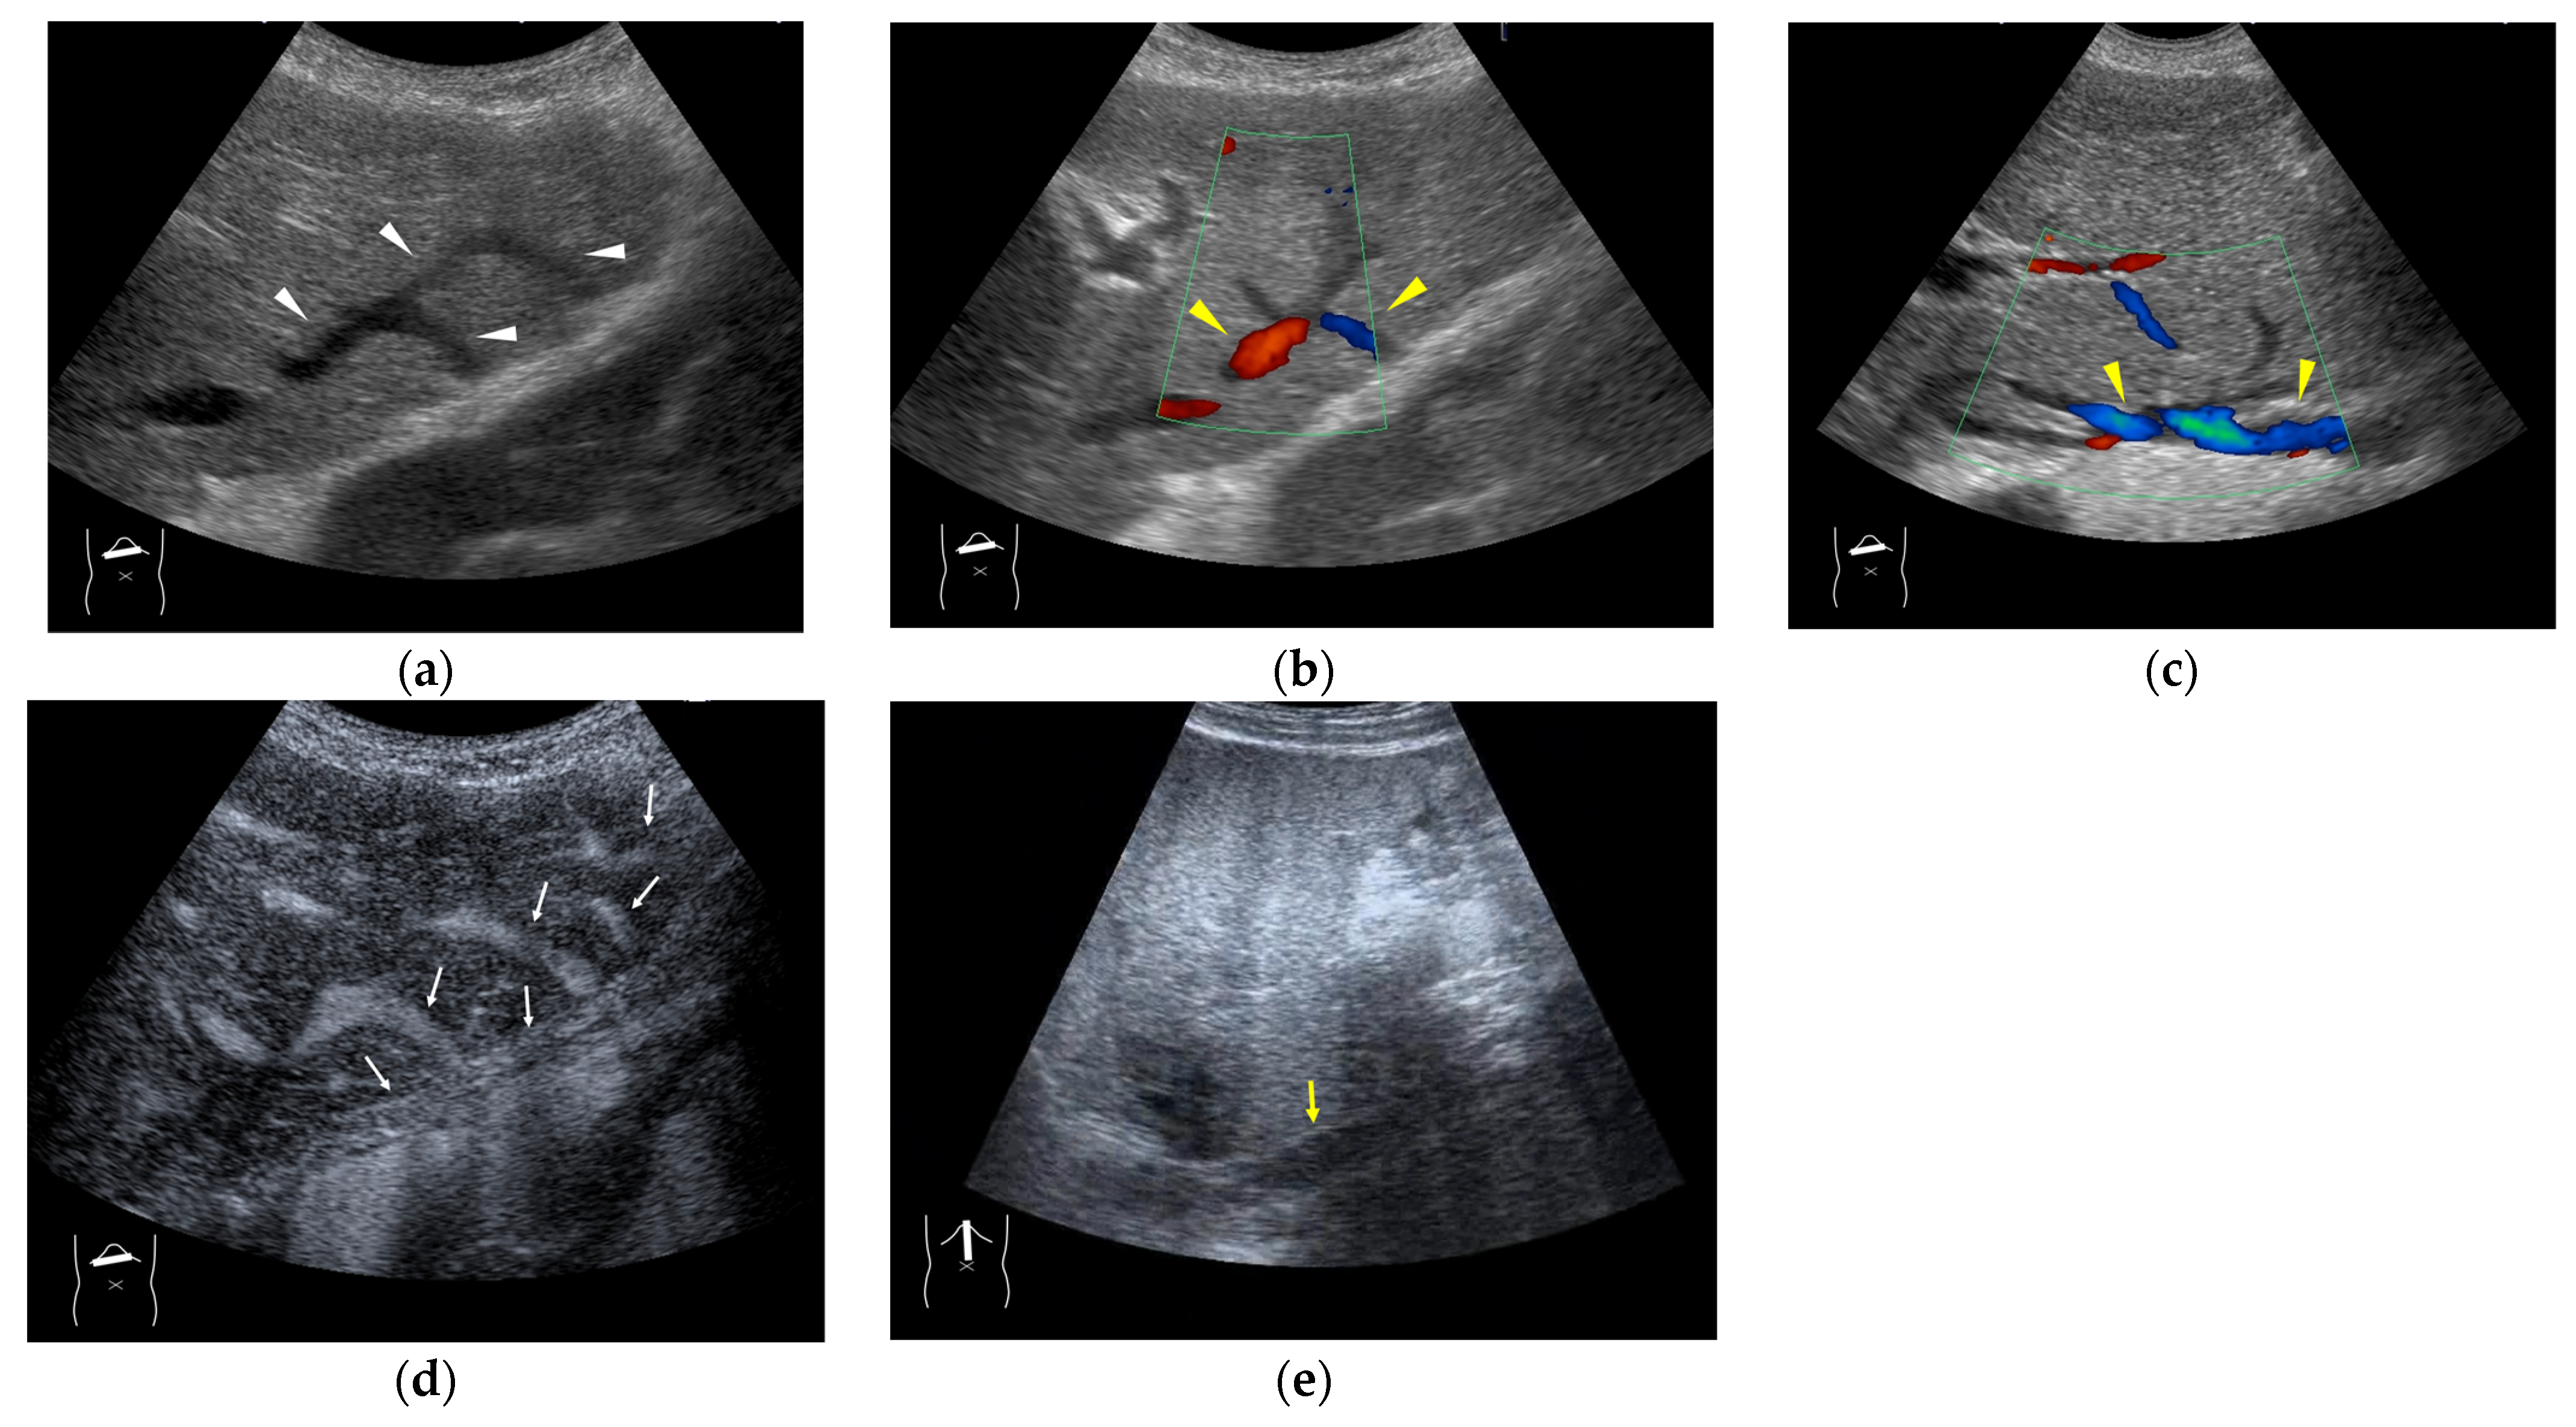

Figure 5.

Representative case of surgically resected solitary metastasis from small bowel sarcomatous adenocarcinoma: (a) The lesion (arrow heads) is well demarcated on B-mode US. (b,c) It is homogeneously hyper-enhanced (white arrows) in the arterial phase, and the tumor size appears to increase (yellow arrows), probably due to many surrounding fine vascular shunts.